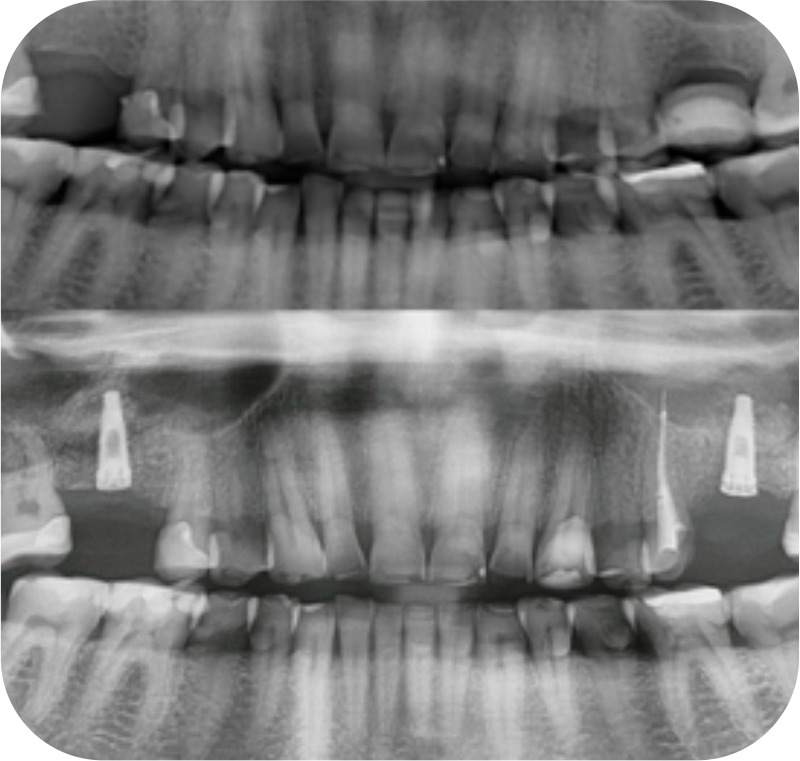

Descolamento da membrana de Schneider, seleção do tipo de enxerto, condições ideais para colocar o implante e locais de incisão são uma dificuldade para você?

Planeje antes de executar! O que parece complicado, você vai fazer de uma forma replicável e descomplicada na Imersão Sinus. Tenha a confiança e conhecimento necessário para planejar com excelência as técnicas de Sinus Lift.

A Imersão traz um dia completo de treinamento sobre as técnicas, biomateriais e sutura, para que você pratique e simule todos os movimentos delicados que envolvem o Levantamento de Seio Maxilar.